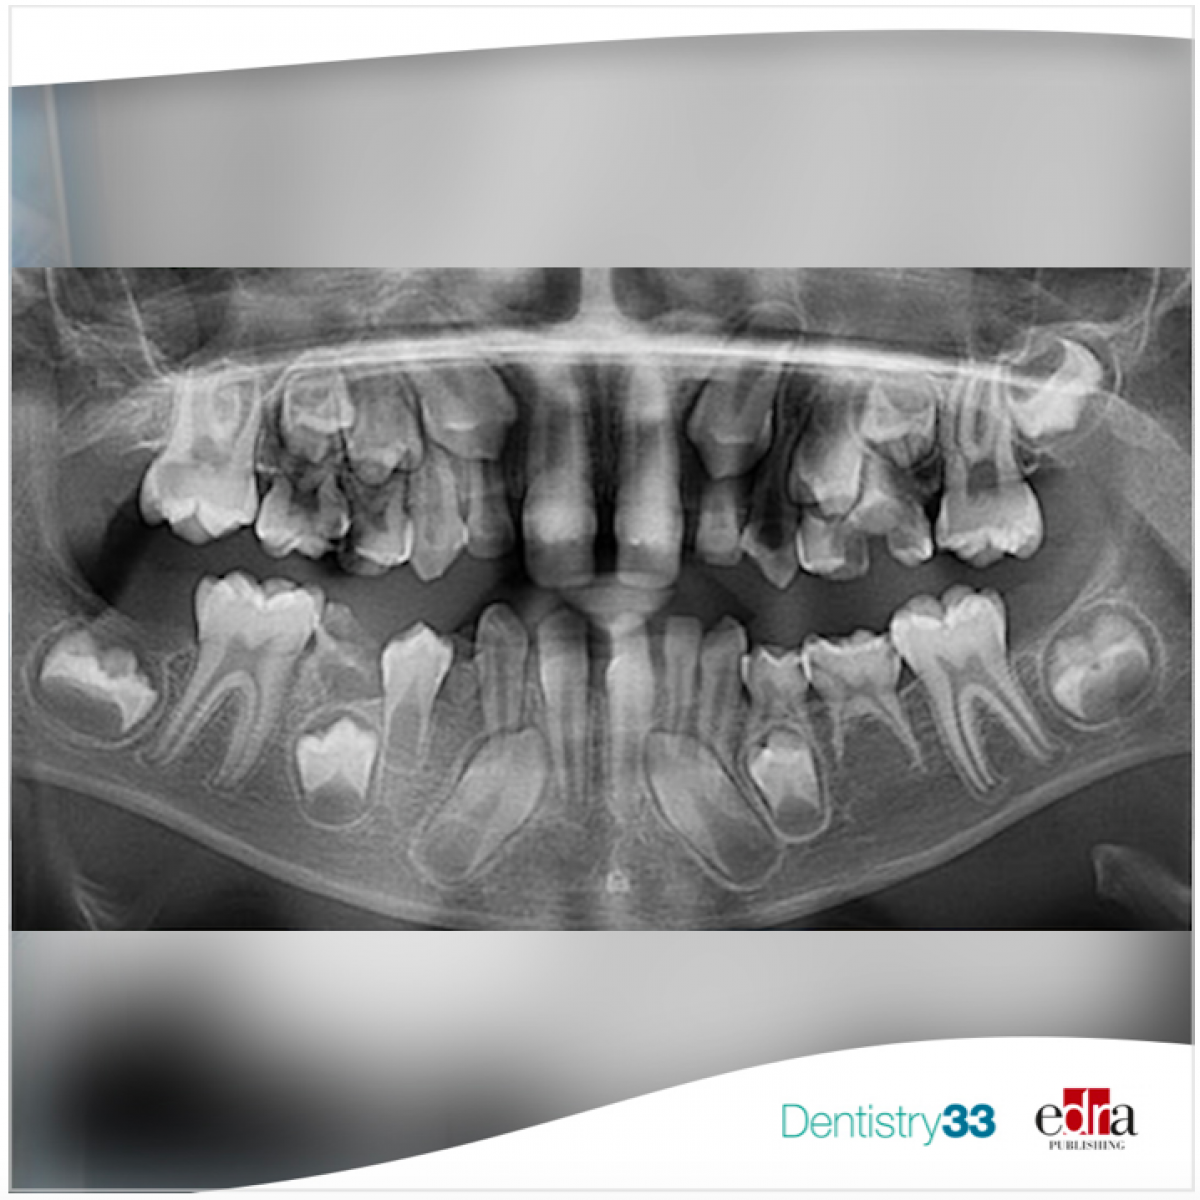

PFE is defined as incomplete tooth eruption despite the presence of a clear eruption pathway. The primary failure eruption (PFE) was first described by Proffit and Vig in 1981, in which nonankylosed teeth fail to erupt owing to malfunction of the eruption mechanism. Mostly posterior teeth are affected, leading to a posterior open bite. The tooth affected by PFE is likely to become ankylosed when orthodontic force is applied. The disease is commonly seen unilaterally but bilateral involvement has also been reported. The cause of PFE is still not clear, but genetic predisposition is often implicated.

17 articles reporting on PFE were included. These articles contain case reports (n = 5), case series (n = 3), observational study (n = 5), and retrospective analysis (n = 4). Overall, 314 patients were studied. In all the reported cases, the molars were affected. In 38 cases (24.3%), the primary teeth were affected, while in 118 patients (75.7%), the deciduous teeth were not affected. In 39 cases, additional dental anomalies were described.

No studies reported PFE in teeth other than molars and premolars, indicating that PFE only affects these teeth.

As deciduous teeth were impacted by PFE in 38 patients, it can be said that PFE affects both dentitions. The dental anomaly most commonly reported in this study is alteration in the root morphology (n = 11), but the small number of reported cases indicates that additional dental anomalies are not significantly associate with PFE.

Infraocclusion of the posterior teeth of both sides, could help differentiate PFE from isolated ankylosis, which affects usually only one arch.